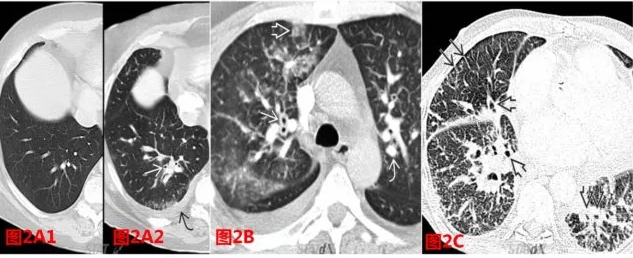

圖 3  心源性肺水腫典型表現(xiàn):小葉間隔

影像學(xué)上所說的肺小葉是多指次級肺小葉(圖 3A),是肺結(jié)構(gòu)的最小獨(dú)立單位,以結(jié)締組織間隔為邊緣,由小的小葉細(xì)支氣管和肺動脈支配,是解釋 HRCT 表現(xiàn)的關(guān)鍵解剖結(jié)構(gòu)。圖 3B1 中白箭所指即為小葉間隔。

圖 4  心源性肺水腫典型表現(xiàn):小葉間隔增厚

心衰發(fā)生后,由于構(gòu)成小葉間隔的間隔靜脈和淋巴管回流不暢,小葉間隔厚度增加(對比同一層面,圖 3B2 中的小葉間隔明顯增厚),這也就是胸片 kerleyB 線的形成原理(圖 4A)。圖 4B/C/D 所示即是 CT 圖像上心衰引起的小葉間隔增厚的典型征象。

同理,心衰發(fā)生后,患者的 CT 表現(xiàn)上也常可出現(xiàn)胸膜葉間裂的增厚和模糊(圖 5)